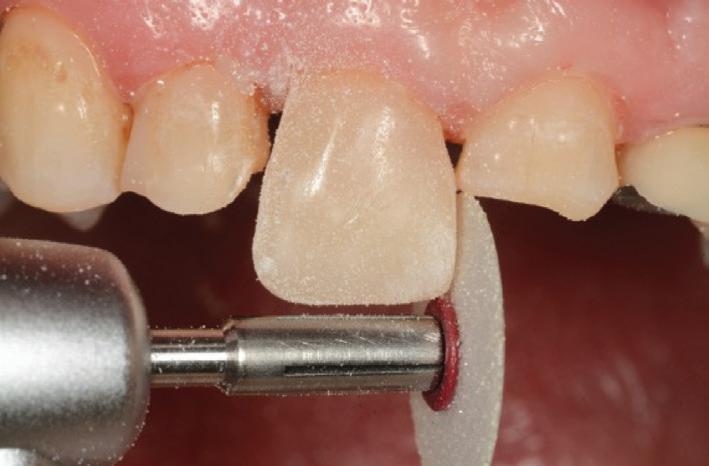

Finally, a superficial layer of enamel shaded composite (A2E) was applied (Fig.12), shaped and cured, before reshaping of the tooth was performed with OptidiscTM system (Fig. 13).

After all of the teeth were restored (except for the upper left premolars which were to be extracted), final shaping and polishing procedures were instigated using OptidiscTM, IdentoflexTM and HiLuster PLUS polishing systems (Fig. 18).